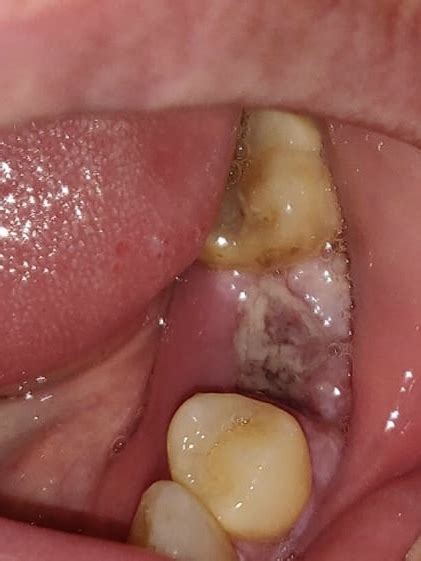

white stuff after tooth pulled

white stuff after tooth pulled. There are any references about white stuff after tooth pulled in here. you can look below.